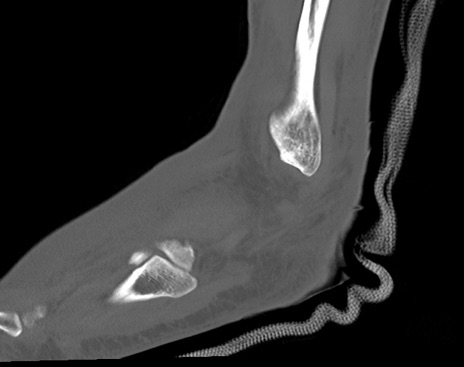

症例37 左足関節CT(矢状断像)

左足関節CT

横断像